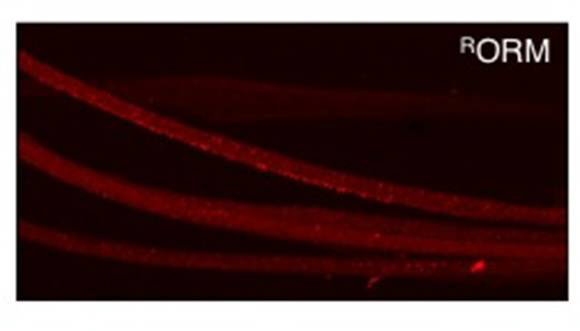

It's exactly what University at Buffalo researcher Shermali Gunawardena was hoping to see: It meant that ORMOSIL, a novel class of nanoparticles, had successfully penetrated the insects' brains. And even after long-term exposure, the cells and the flies themselves remained unharmed.

The particles, which are tagged with fluorescent proteins, hold promise as a potential vehicle for drug delivery.

"We saw that after feeding these nanoparticles in the fruit fly larvae, the ORMOSIL was going mainly into the guts and skin. But over time, in adult flies, you could see it in the brain. These results are really fascinating because these particles do not show any toxic effects on the whole organism or the neuronal cells," said Gunawardena, an assistant professor of biological sciences and a researcher in UB's Institute for Lasers, Photonics and Biophotonics.